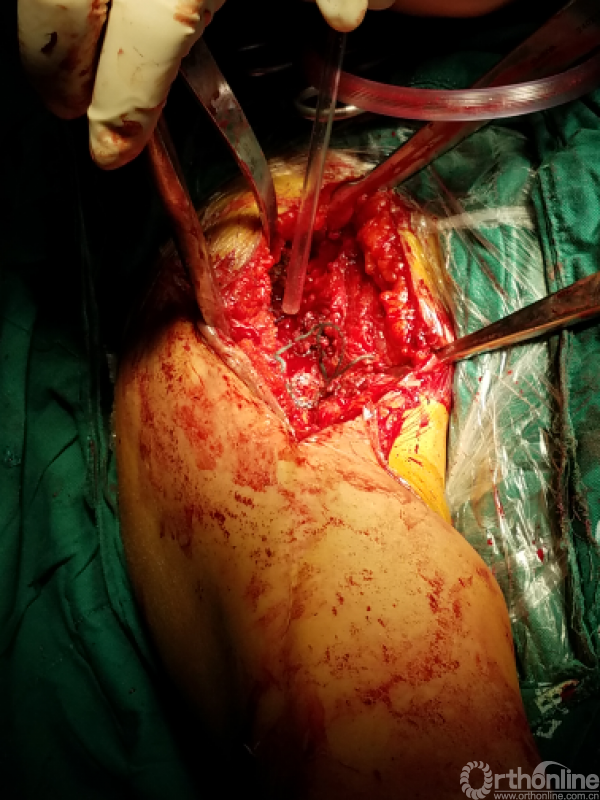

困难重重:

1、广泛粘连,解剖层次不清

2、广泛点状出血灶

3、分不清间隙

4、盂肱关节正常结构位置改变,关节囊瘢痕挛缩替代

5、屈曲外旋看不见关节间隙活动

手术过程:

1.从近端关节前外侧逐步下行,切除瘢痕

2.用食指逐步探查

3.以骨面硬质感为基准从中央部位向两侧分离

4.骨撬,骨膜剥离器协助分离内外侧间隙

5.以缺损处为中心向四周扩大显露

咬出增生骨痂及清理瘢痕组织后显露出原肩袖缝线,杂乱,完整,表面见有脓性组织

瘢痕发硬,变性,周围包裹纤维软骨痂

由于解剖结构紊乱,头静脉已消失。旋肱后动脉,弓状动脉剥离时出血,位于外侧转弯处,行填塞止血。

显露出肱骨头假体柄处

开始向内上扩大显露

注意事项:  肱骨头内移至喙突处,位于后内侧下方已有骨桥连接

特别小心腋鞘及臂丛神经

提示无法顺利脱位!!!

小心咬出间隙后,牵引肘关节前屈肩关节后伸外旋,拉钩撬拨脱位!!

关节盂正常结构消失,至喙突偏内侧部位,上方紧贴肩峰下,仍然有骨质可用!

咬除连接骨桥,清理髓腔,恢复活动度